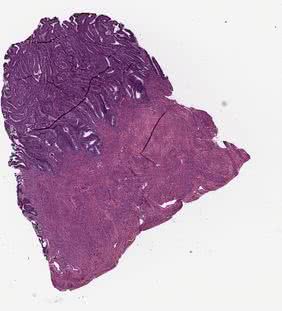

raw_small

Original tissue image saved with the magnification defined by the --vis_mag parameter.

_images/raw_small.jpg